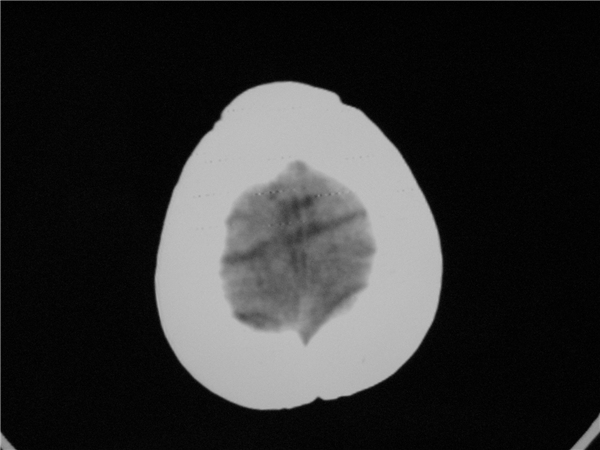

标题: PED2843: CT-23675 F 4Y 大家看看颅内有问题没。 [打印本页]

标题: PED2843: CT-23675 F 4Y 大家看看颅内有问题没。

四脑室扩大,三脑室稍扩大上移

胼胝体发育不全??

六脑室

四脑室扩大,,六脑室

四脑室扩大,密度降低,图像的问题?建议mr扫描。